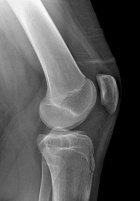

D.E. - 15 year old male with left knee pain after falling from a skateboard three weeks ago